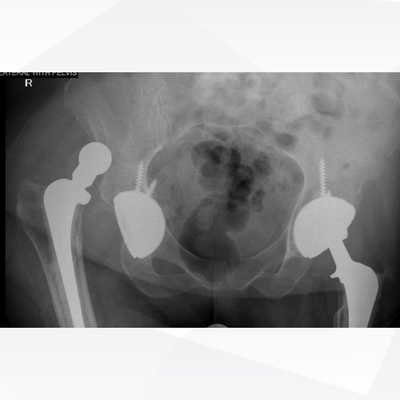

Click on an image below to view more info.